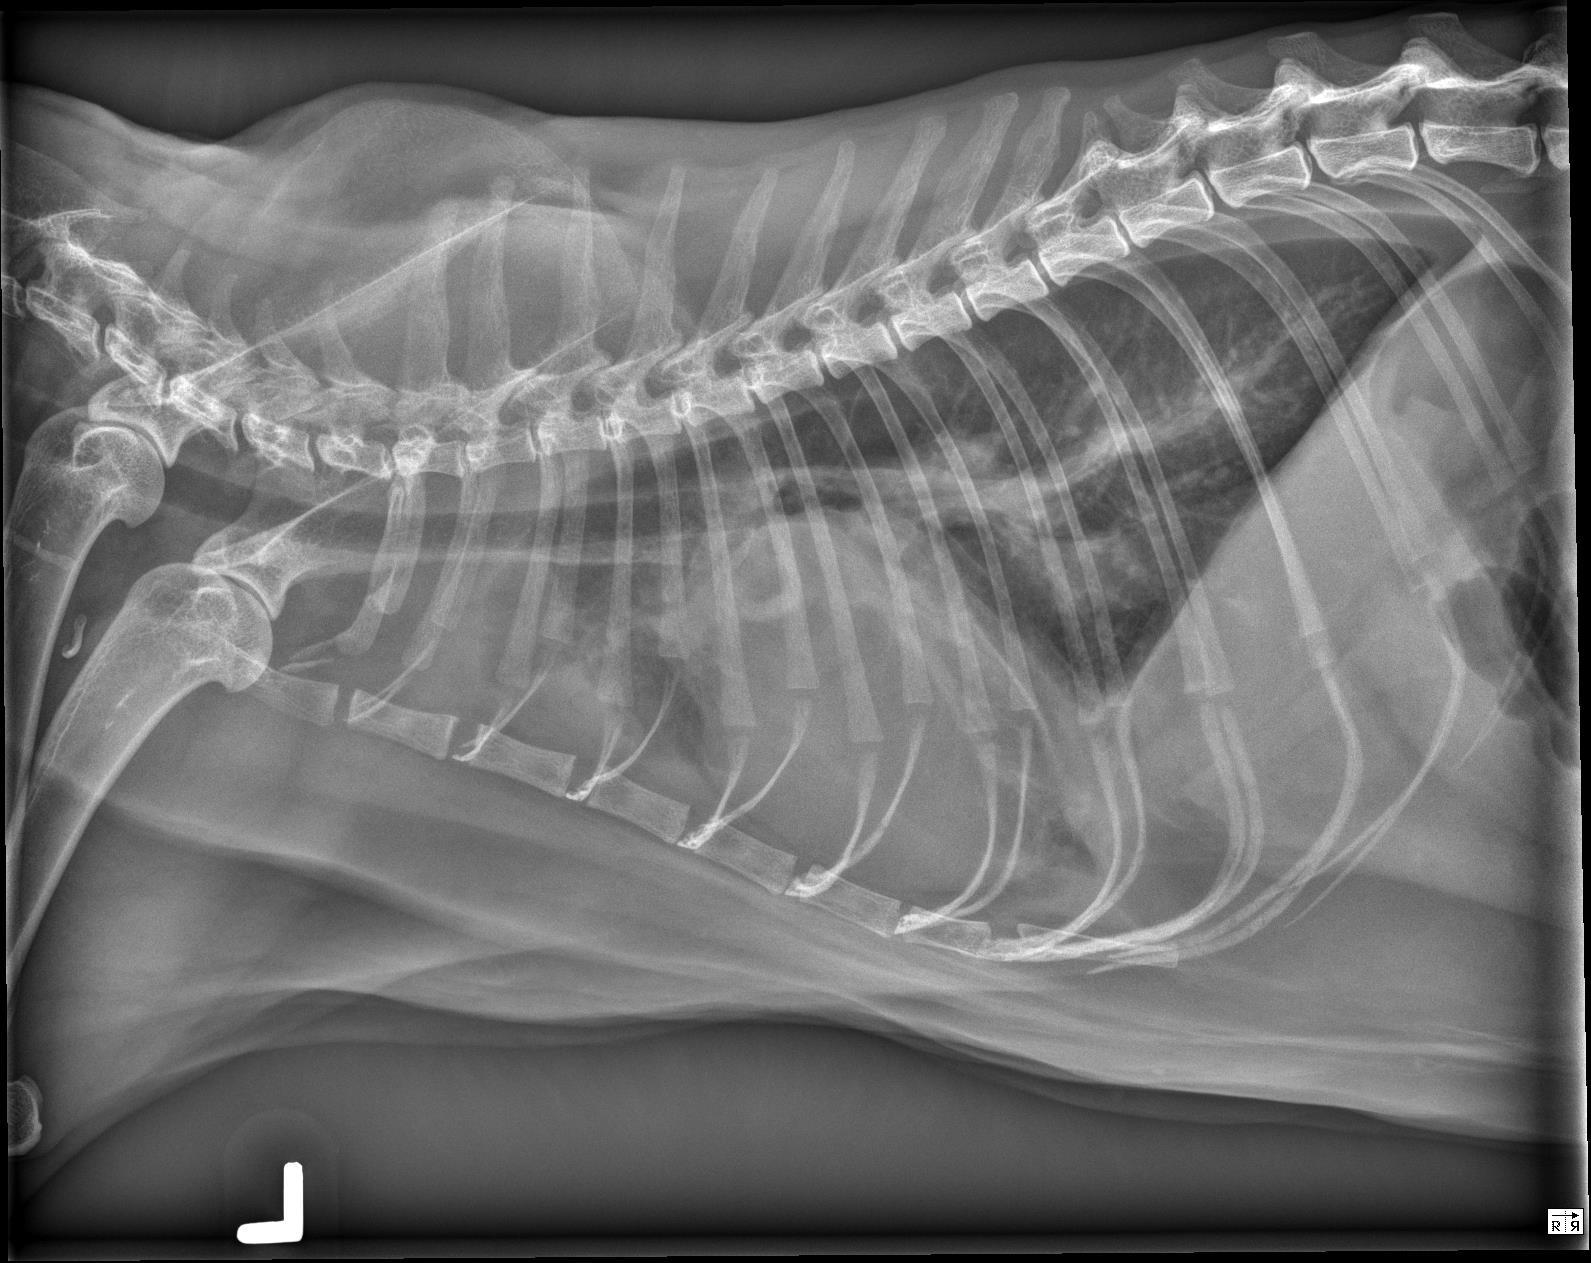

The cardiac silhouette is moderately to severely enlarged occupying greater than 2/3 the height of the thoracic cavity and almost the entire width of the thoracic cavity on the ventrodorsal radiograph. The right cranial lobar pulmonary vein is mildly enlarged compared to the corresponding artery. The pulmonary arteries are enlarged and mildly tortuous. There is a mild, diffuse unstructured interstitial to bronchointerstitial pulmonary pattern.

There is a small volume of fluid in the pleural space of both hemithoraces which widens the pleural fissures. The cranial mediastinum is widened on the ventrodorsal radiograph and there is a focal, rounded, soft tissue opaque convexity immediately dorsal to the second sternebra. There is a small volume of incidental gas within the intrathoracic esophagus.

Severe cardiomegaly in conjunction with the enlarged right cranial lobar vein, pleural effusion and diffuse unstructured interstitial pulmonary pattern is most concerning for congestive heart failure from underlying cardiomyopathy and/or fluid overload. Echocardiography is recommended for further evaluation. The mild tortuosity of the pulmonary arteries may be a patient variant or represent a component of cardiovascular disease (vs. pulmonary hypertension). – The soft tissue convexity immediately dorsal to the second sternebra may represent an enlarged sternal lymph node or loculated pleural effusion.